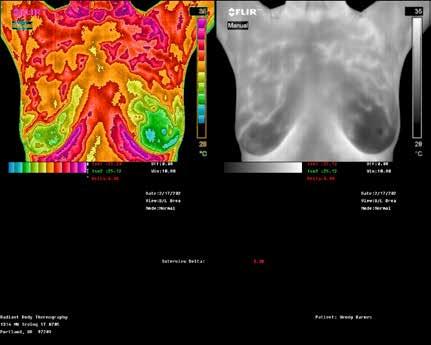

EMERALD COAST THERMOGRAPHY

850-980-1005

EmeraldCoastThermography.com

Radiation-free health scans to detect potential issues early. Safe, no-touch, and physician referralfree thermography services are available.